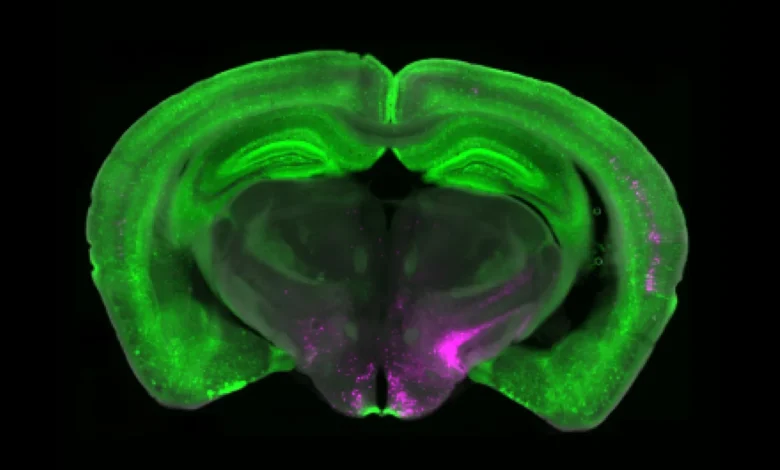

Pedley descobriu uma parte importante do quebra-cabeça da dor crônica, juntamente com as Cooperativas da Universidade de Pitley, da Universidade de Pittsburg e do Instituto das Escrituras. Suas células específicas do sistema cerebral de aceitação Y1 (Y1R)-A, também conhecidas como neurônios, estão localizadas no núcleo paraférico lateral (LPN). Esses neurônios são ativados em uma série de condições de dor, mas também processam os sinais de fome, medo e sede. Isso sugere que as respostas à dor cerebral podem ser ajustadas quando se concentra em requisitos de alta emergência.

A equipe de Pedley, que trabalhou com o Laboratório Taylor da Universidade de Pittsburg, usou imagens de cálcio para exibir neurônios em tempo real de amostras de animais com dor de curto e longo prazo. Eles notaram que os neurônios Y1R não reagiam rapidamente às erupções de dor; Em vez disso, um evento chamado “atividade tônica” foi um disparo constante durante a dor crônica.

Os pesquisadores também classificaram a identidade molecular e anatômica dos neurônios Y1R no LPPN. Eles descobriram que os neurônios Y1 não formavam duas populações anatômicas ou moleculares elegantes. Em vez disso, esses neurônios estão espalhados em muitas células.

“É como observar carros num estacionamento”, diz Bedley. “Esperávamos que todos os neurônios Y1R fossem aglomerados de carros amarelos estacionados juntos, mas aqui os neurônios Y1R são como a tinta amarela distribuída por carros vermelhos, carros azuis e carros verdes. Não sabemos exatamente Por queMas pensamos que esta distribuição em mosaico permitirá ao cérebro reduzir vários tipos de entradas dolorosas em muitas rodadas. “